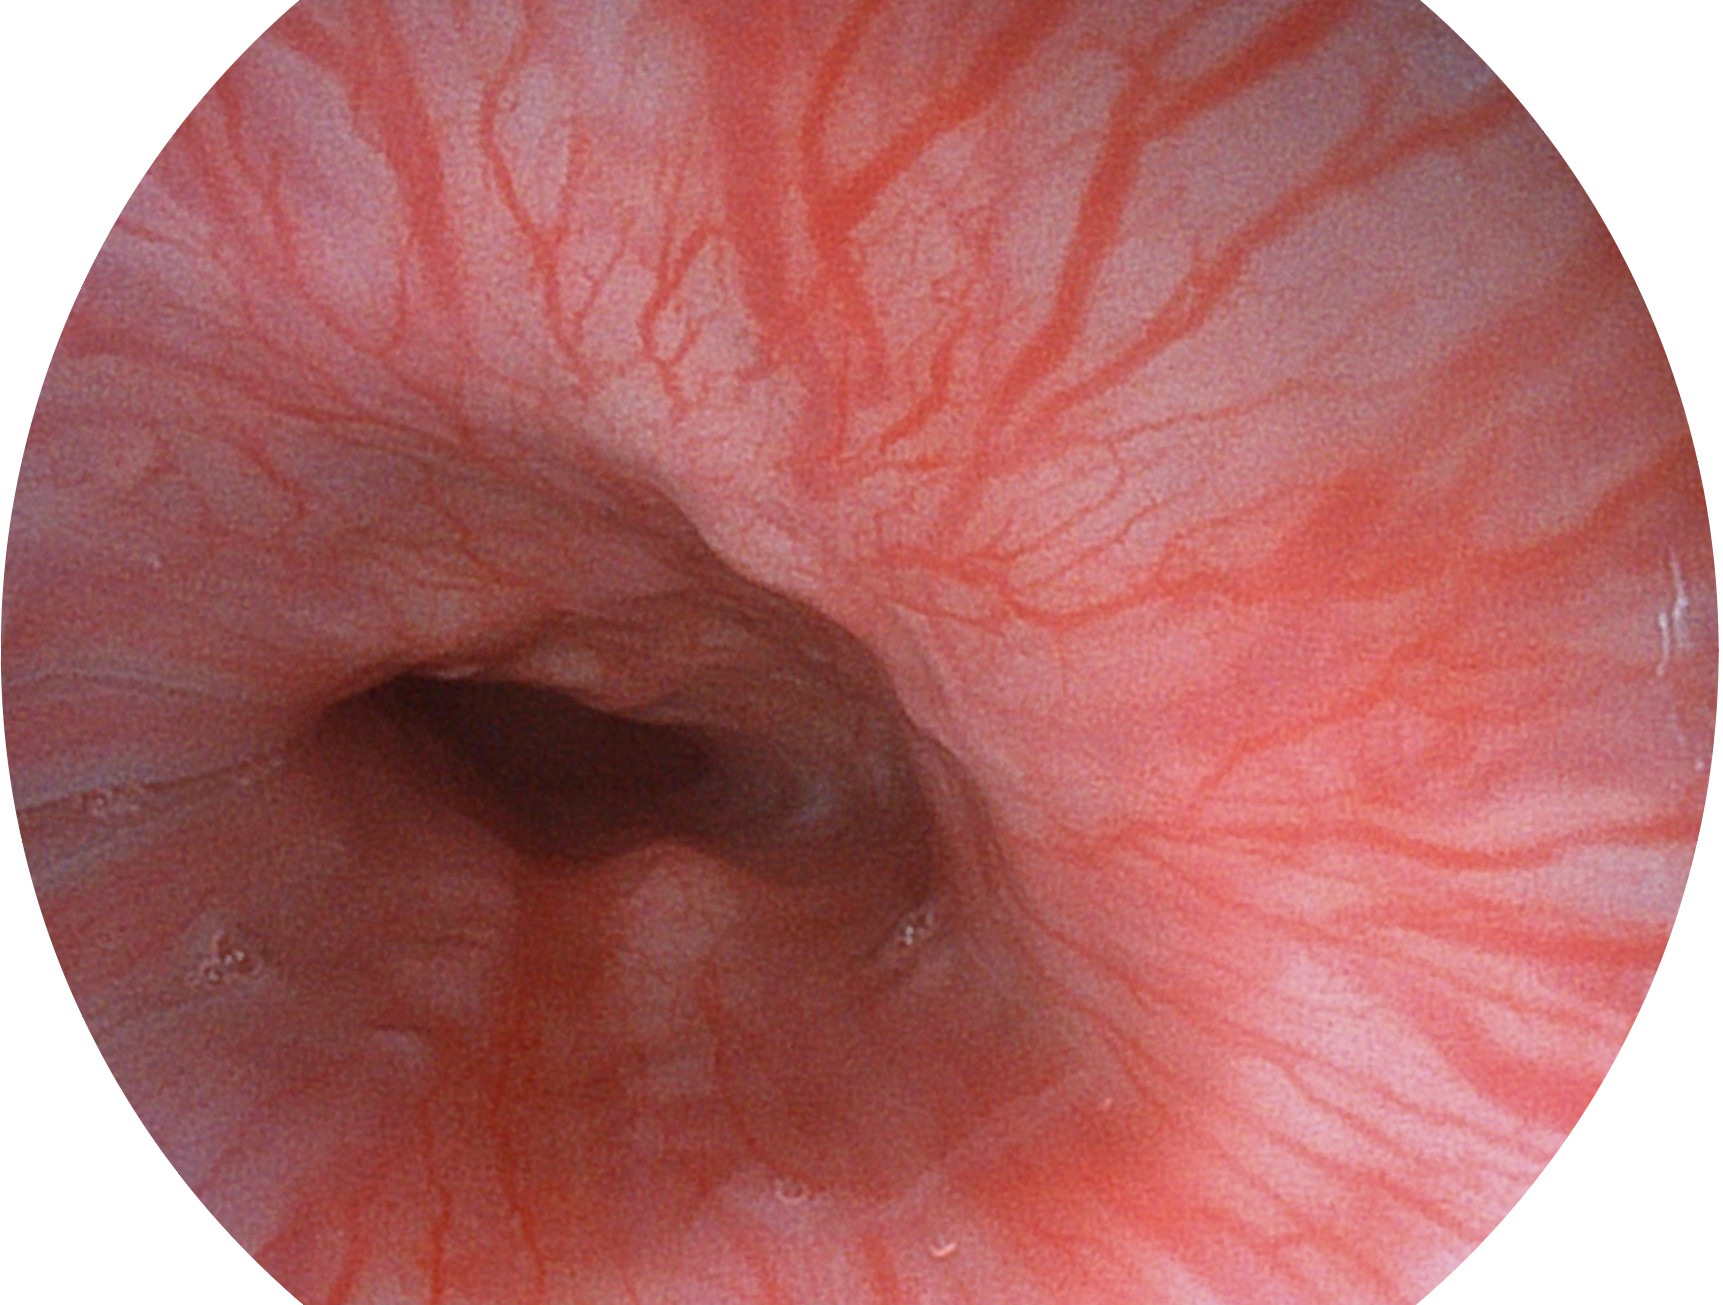

云顶集团官网新开发的内镜染色技术,主要是基于多波长LED 光源的开发,VLS-55Q 四波长LED 光源是由四个不同颜色的LED光按照相应照明模式所规定的特定发光比例进行合束后形成,合束后形成的照明光的光谱由红光、绿光、蓝光及蓝紫光这四个不同的波段范围构成。具有更高光谱自由度,通过光谱比例的控制,实现了聚谱成像技术,英文全称为“Spectral Focused Imaging, SFI”,缩写为“SFI”和光电复合染色成像技术,英文全称为“Versatile Intelligent Staining Technology, VIST”,缩写为“VIST”。